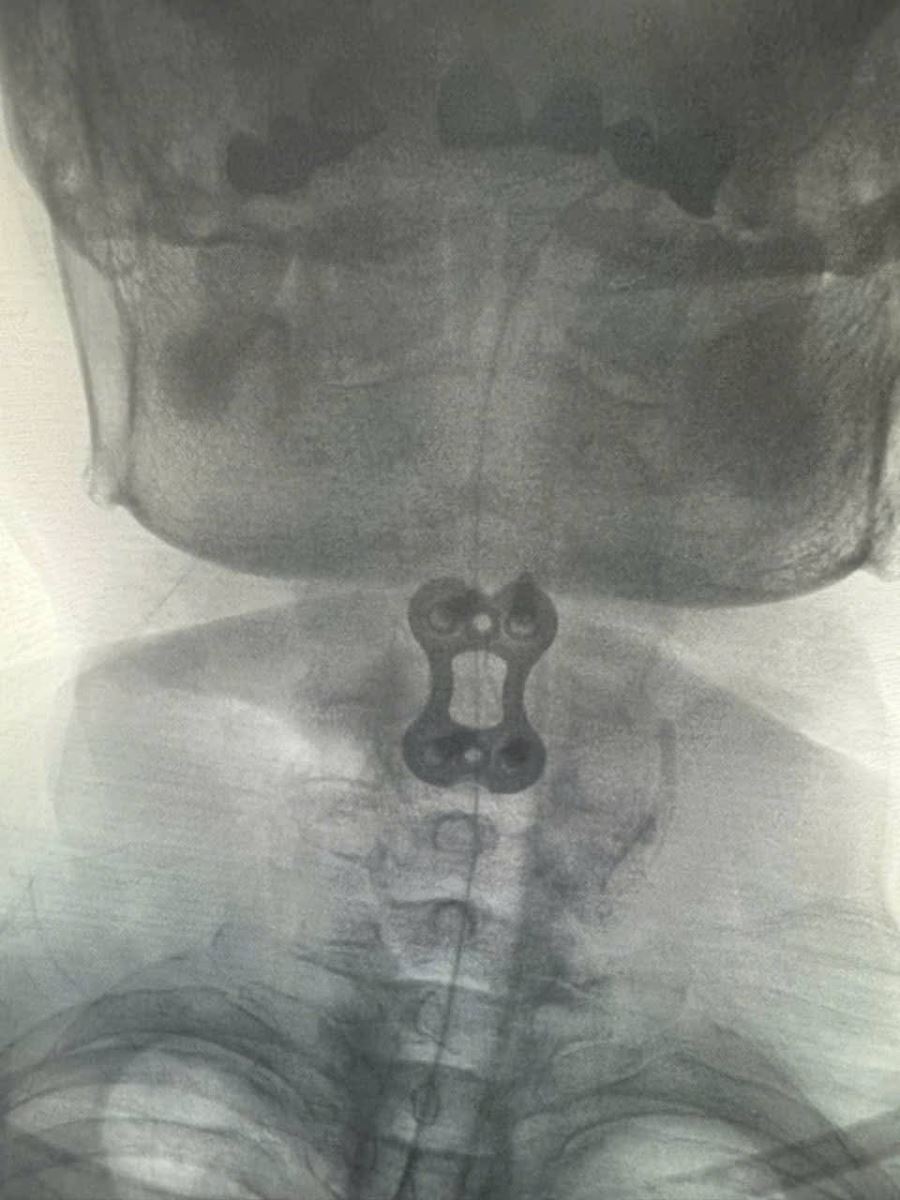

Bệnh nhân được phẫu thuật ACDF C3–C4 (lấy nhân đĩa đệm thoát vị, giải phóng chèn ép tủy – rễ thần kinh, hàn xương và cố định cột sống cổ lối trước).

Sau mổ: tê bì hai tay giảm rõ rệt, cơ lực cải thiện, tình trạng thần kinh ổn định.